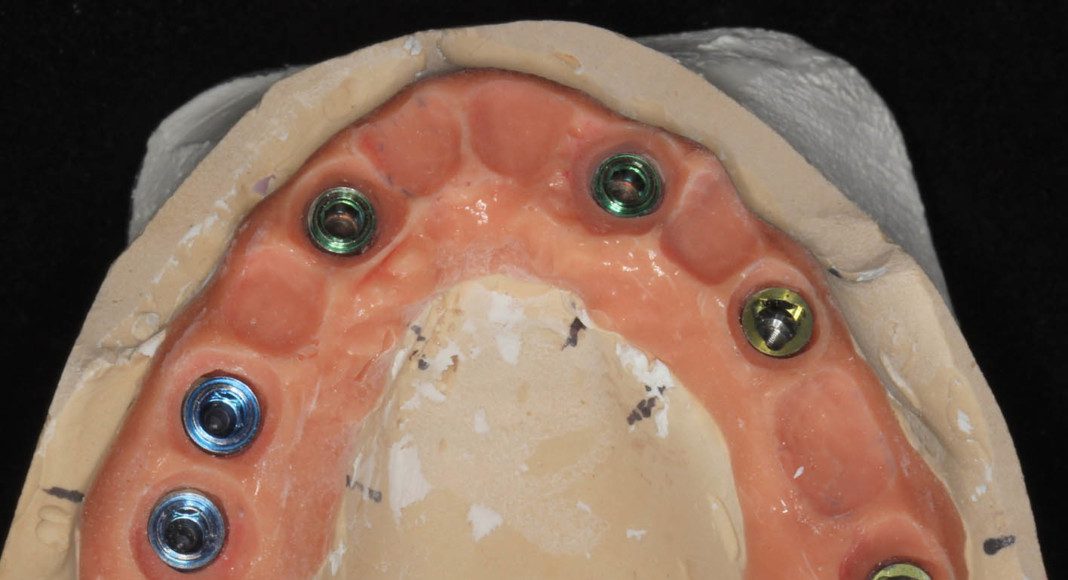

Occlusal view of implants in mouth. The gum tissues have matured very nicely and are ideal recipient sites for the zirconia bridge.

Occlusal view, day of delivery. If you look closely, you can see the final prosthetic screw (blue). This channel is covered with composite resin and patient comfort.